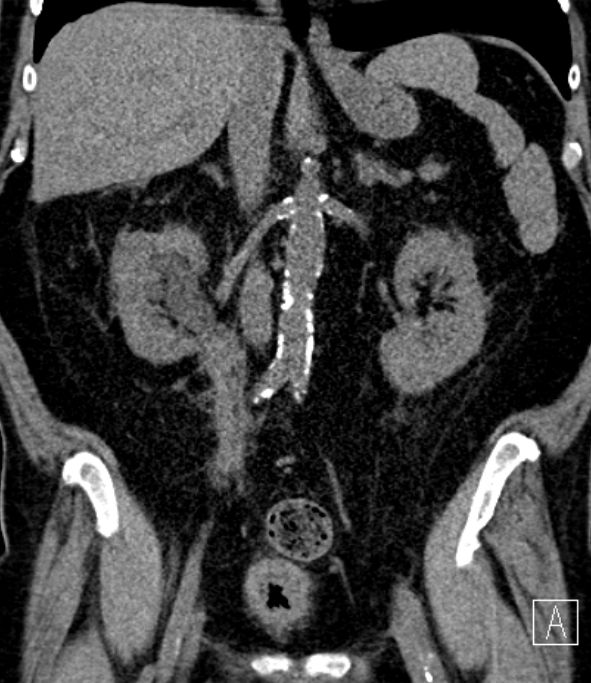

Urothelkarzinom der Niere 81-jährige Frau mit einem großen, die linke Niere einnehmendem Tumor. Histologie: Urothelkarzinom.

Die linke Nierenarterie ist von LK-Metastasen eingeschlossen.